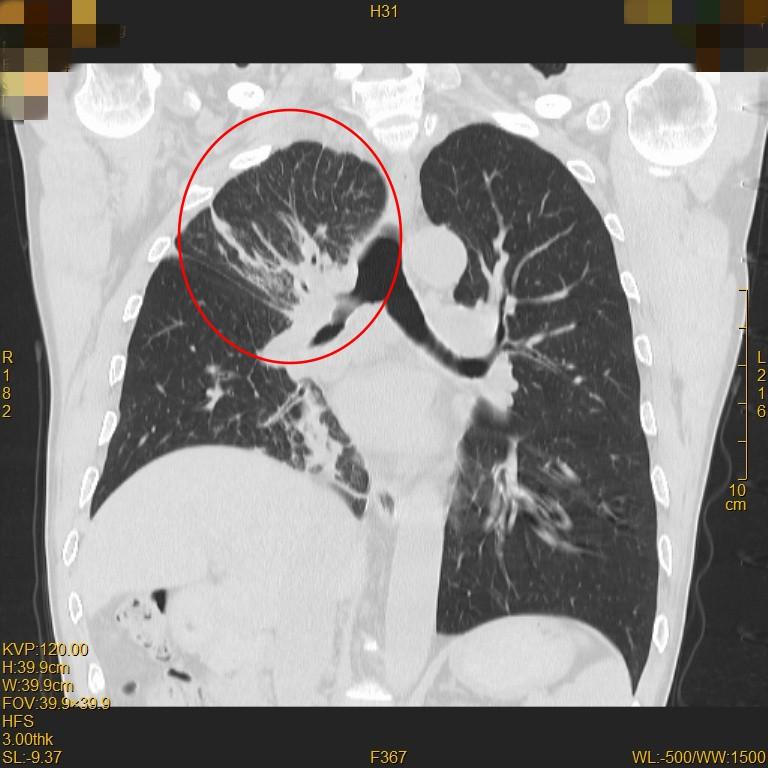

▲治疗前右肺上叶不张

▲治疗后肺复张